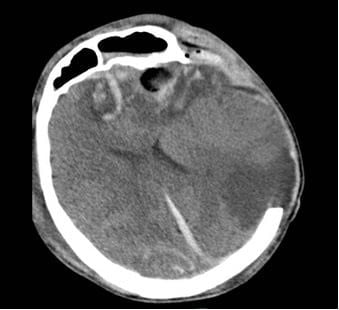

Phim CT não của 2 bệnh nhân

Tại Bệnh viện Nhân dân 115, bệnh nhân G.A nhập viện trong tình trạng hôn mê sâu, phải thở máy nội khí quản. Kết quả chụp CT sọ não cho thấy dập não xuất huyết rải rác nhiều vị trí, phù não lan tỏa nặng, tiên lượng rất dè dặt, nguy cơ tử vong cao. Bệnh nhân được điều trị tích cực tại Đơn vị Hồi sức ngoại khoa, Khoa Gây mê Hồi sức với sự theo dõi sát sao của ê-kíp chuyên môn.